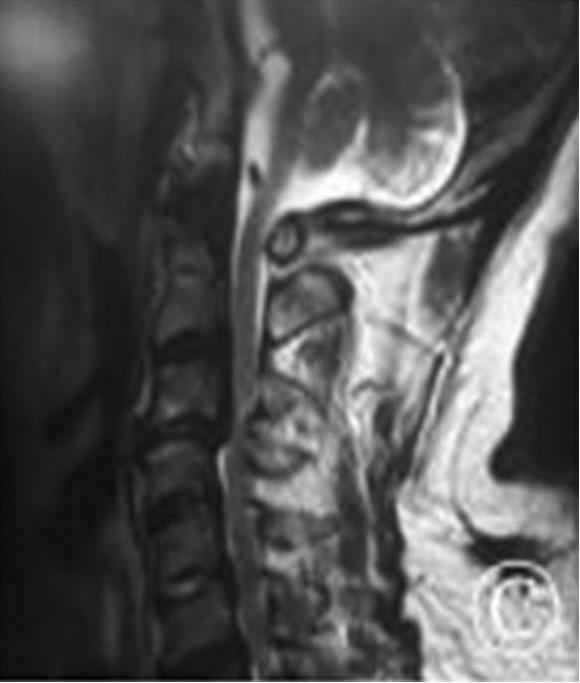

2.辅助检查 头颅CT未见明确梗死及出血灶(图5-1)。

6.辅助检查:头颅CT未见明确梗死及出血灶(图5-1)。头颅MRI+DWI显示双侧基底节区、双侧大脑半球白质多发腔隙性梗死,DWI序列未见急性梗死;脑白质稀疏、脑萎缩;全副鼻窦炎,双侧下鼻甲肥大;双侧乳突窦炎。颈椎MRI平扫提示颈椎退行性变,C2/3、C3/4、C4/5、C5/6椎间盘突出,颈椎骨质增生;C3/4椎管狭窄,脊髓水肿,C3/4椎间盘层面脊髓损伤。

图5-1 头颅CT平扫未见明显梗死及出血灶